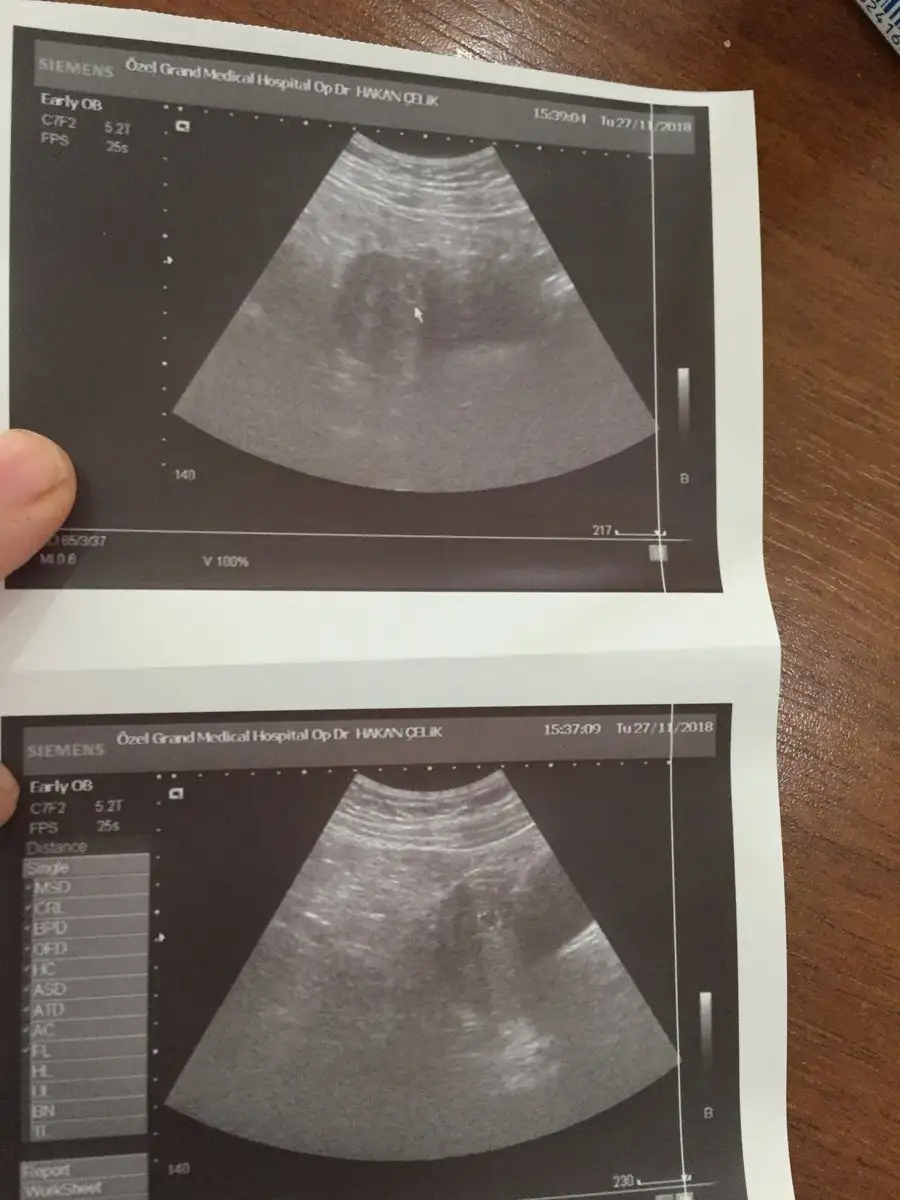

Merhaba kizlar bu gün kesem gözüktü 4+6 dedi doktor burdan biri kese hangi taraftaysa ona göre cinsiyet tahmin ediyordu kimdi o

Eklentiler

• 48E4F86F-D574-4D35-9ABA-B5A04B8A0741.webp

• 561EC29F-59CA-4966-A730-A51A0998CE40.webp